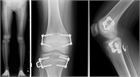

1. 小学校就学前に3㎝程度の脚長差が発生する可能性が高い患児は創外固定器による脚延長を行い、延長側を1㎝程度余分に行い就学前に治療を終了する。その後脚長差が再発した場合は第2次成長期に8 plateによる成長抑制術を行うように計画することが最も負担が少ない治療法である。